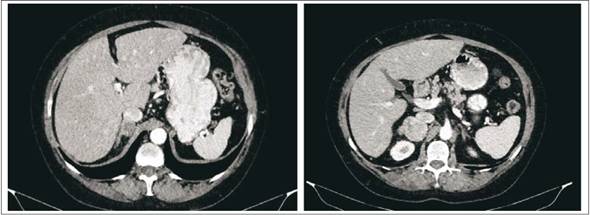

En todos los casos se trataba de lesiones unilaterales, con un tamaño promedio de 6 cm (rango 2-12 cm).(Figura 2)

En todos los pacientes se realizó una tomografía computada como método imagenológico para orientación diagnóstica, destacando que en la gran mayoría de ellos fue la TAC el estudio inicial en el que se identificó la lesión suprarrenal por primera vez, por lo que no fue necesario repetirla. En dos pacientes no fue la tomografía el estudio que detectó la imagen suprarrenal, tratándose en un caso de un politraumatizado donde la ecografía abdominal reveló la masa adrenal, y en el otro una enterorresonancia magnética realizada a una paciente con enfermedad celíaca. A excepción de estos dos pacientes y de otros dos en los que se solicitó el estudio por la presencia de litiasis renal (cólico nefrítico), en los 12 restantes el motivo de solicitud de imagenología abdo minal fue la presencia de dolor abdominal inespe cífico.

Con respecto a la imagenología, constituye la llave diagnóstica, contando con estudios morfológicos (tomografía y resonancia magnética) y funcionales (centellograma y PET-scan). La tomografía computada utilizando cortes finos va a determinar el tamaño de la lesión y sus relaciones con estructuras y órganos adyacentes. Actualmente se considera de mayor utilidad el protocolo cuadrifásico6 (fases sin contraste, arterial, portal y tardía a los 5 minutos). Interesan tres criterios fundamentalmente: el tamaño de la lesión, la densidad sin contraste, y el realce tardío a los 10-15 min luego de la inyección de contraste para calcular el wash-out absoluto y relativo. En la fase sin contraste, la densidad ayuda a distinguir lesiones benignas (con alto contenido graso en más del 70% de los casos), de las malignas, con una sensibilidad y especificidad respectivas de 71% y 98%. Se establece un umbral de 10 unidades Hounsfield (UH) por debajo del cual es casi una certeza que se trate de lesiones benignas, aunque se acepta también de un coeficiente de atenuación de 20 UH o menor. El comportamiento de la lesión tras la inyección de contraste resulta de utilidad sobre todo en aquellos adenomas pobres en contenido graso (30%-50% del total, densidad > 10 UH). A partir de esto se calculan los porcentajes de wash-out absoluto y relativo, que son idependientes del contenido lipídico de la lesión. Valores mínimos de reducción del wash-out relativo y absoluto de 40% y 60%, respectivamente, permiten hacer diagnóstico de adenoma con una especificidad de 100%. Los tumores malignos, y en menor medida los feocromocitomas, tienen por lo general una densidad > 10 UH, son heterogéneos e hipervasculares, y presentan un wash-out mucho menor en fase tardía. Los hematomas son espontáneamente hiperdensos sin contraste, los mielolipomas son hipodensos y los quistes son masas redondeadas de paredes finas que no realzan con contraste. En nuestra serie fue clave el estudio imagenológico en la totalidad de los pa cientes, aportando datos fundamentales en cuanto al tamaño y aspecto, determinantes en la mayoría de los casos de la indicación quirúrgica.